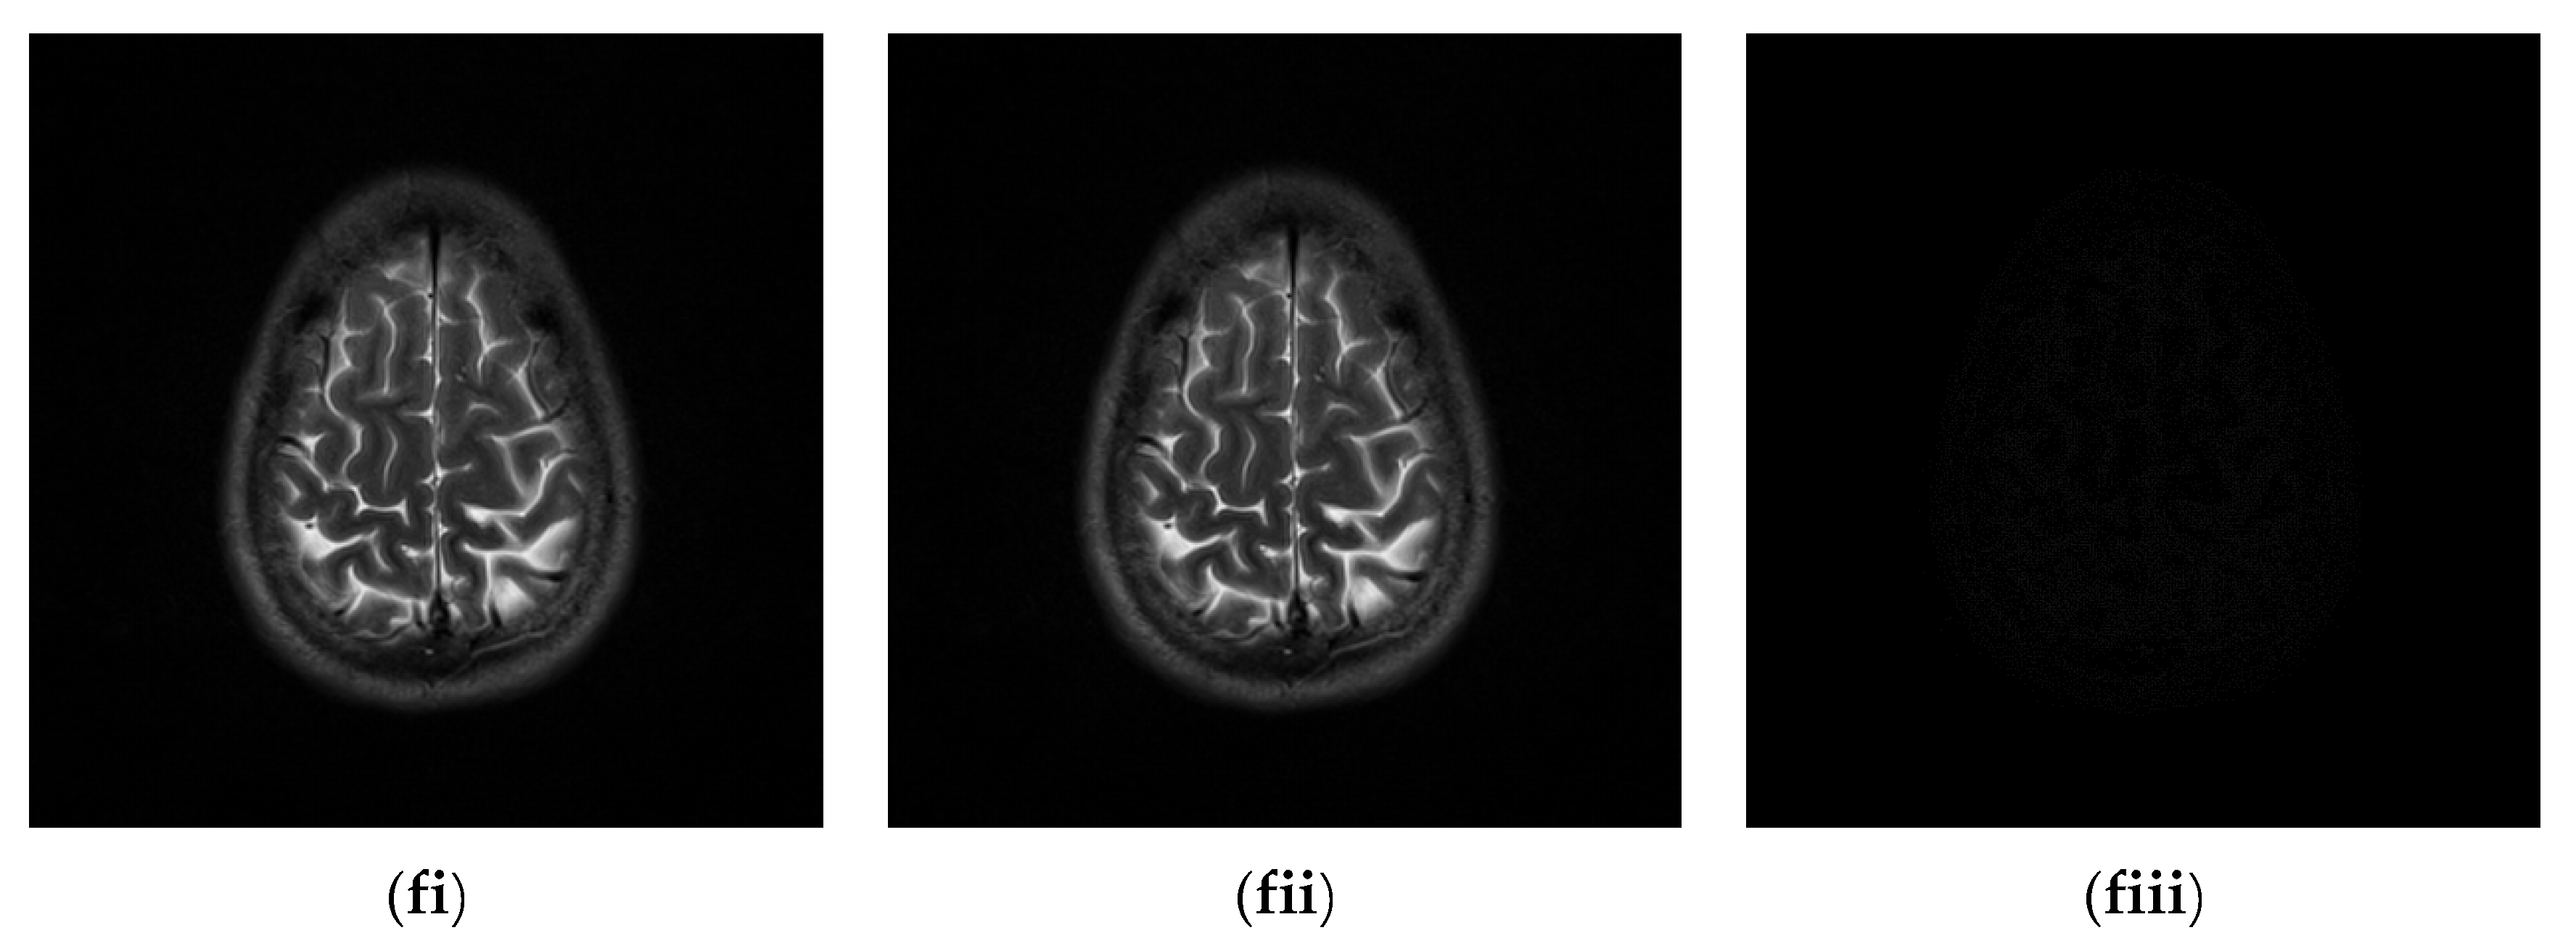

Since the interpolation-based RDH schemes are designed for the special purpose of embedding patient information into medical images, the performance of our proposed adaptive RDH scheme on medical images is the main concern. Figure 11 shows the original image and its corresponding confidential image with 2 bpp secret data embedded, and images showing the difference between the original medical images and their confidential images. The difference images (aiii–fiii) in Figure 11 show almost nothing, which indicates that the proposed scheme does not look much different from the original image after hiding and will not draw the eavesdropper’s attention.

Figure 11.

The original images, the confidential images, and the different images; (ai–fi) The cover images; (aii–fii) The confidential images; (aiii–fiii) The difference between the cover images and the confidential images.